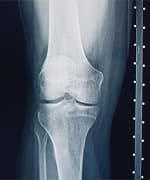

Doctor reviewing knee joint xrays after patietnt took tocotrienols

Tocotrienols to Support Bone Health

Preclinical studies show that tocotrienols could promote formation of cells that build new bone to help restore healthy balance to the bone remodeling process.